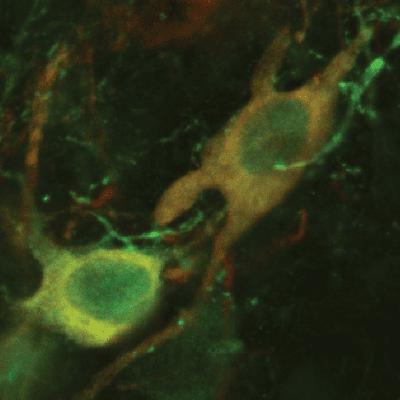

Northwestern Medicine scientists have discovered one of the earliest signs of Parkinson's disease, proving that damaged neuronal mitochondria alone can cause symptoms of the disease, according to a study published in Nature. Senior author D. James Surmeier, chair of the Feinberg department of Neuroscience, who has over 30 years of experience in the field, explains the importance of these findings for future Parkinson's research and therapeutics.